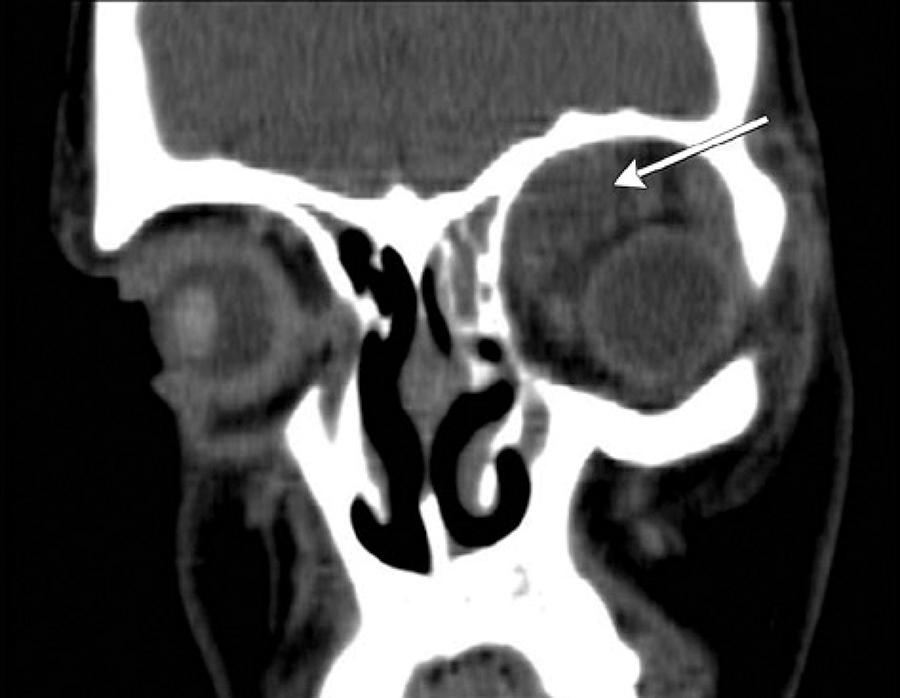

Fifty-one patients met the criteria for the study and had available medical records (29 male, 22 female). Thirty patients were treated on the otorhinolaryngology service and twenty-one patients were treated on the opthalmology service. The age range was 1 to 63 years (mean, 19.92 ± 17.98). Approximately 70% patients (n=36) were younger than 18 years of age. Thirty-two (62.7%) were diagnosed with preseptal cellulitis and 19 (37.3%) were diagnosed with postseptal cellulitis. After detailed evaluations, 15 were diagnosed with a subperiosteal abscess (SPA) and 4 with orbital cellulitis. No one had an intraorbital abscess or a cavernous sinus thrombosis. The age and gender was similar for the two groups. SPA was localized as medial (n=8) (Figure 1), superiomedial (n=4) (Figure 2), inferior (n=1) (Figure 3), and inferiomedial (n=1) (Figure 4). In the postseptal cellulitis group, bilateral pansinusitis was found in 5, unilateral pansinusitis in 6, unilateral maxillary, ethmoid, and frontal sinusitis in 5, unilateral maxillary and ethmoid sinusitis in 2, and unilateral maxillary sinusitis in 1. In the preseptal cellulitis group, bilateral pansinusitis was present in 9, unilateral pansinusitis in 10, unilateral maxillary, ethmoid, and frontal sinusitis in 4, unilateral maxillary, ethmoid sinusitis in 5, and unilateral ethmoid sinusitis in 4 patients. Five patients with medial SPA were treated with endoscopic sinus surgery, one patient with inferior SPA was treated with external surgery, and six patients with other localizations were treated with combination of endoscopic sinus surgery and external surgery. The seasonal distribution of this pathology is shown in figure 5.